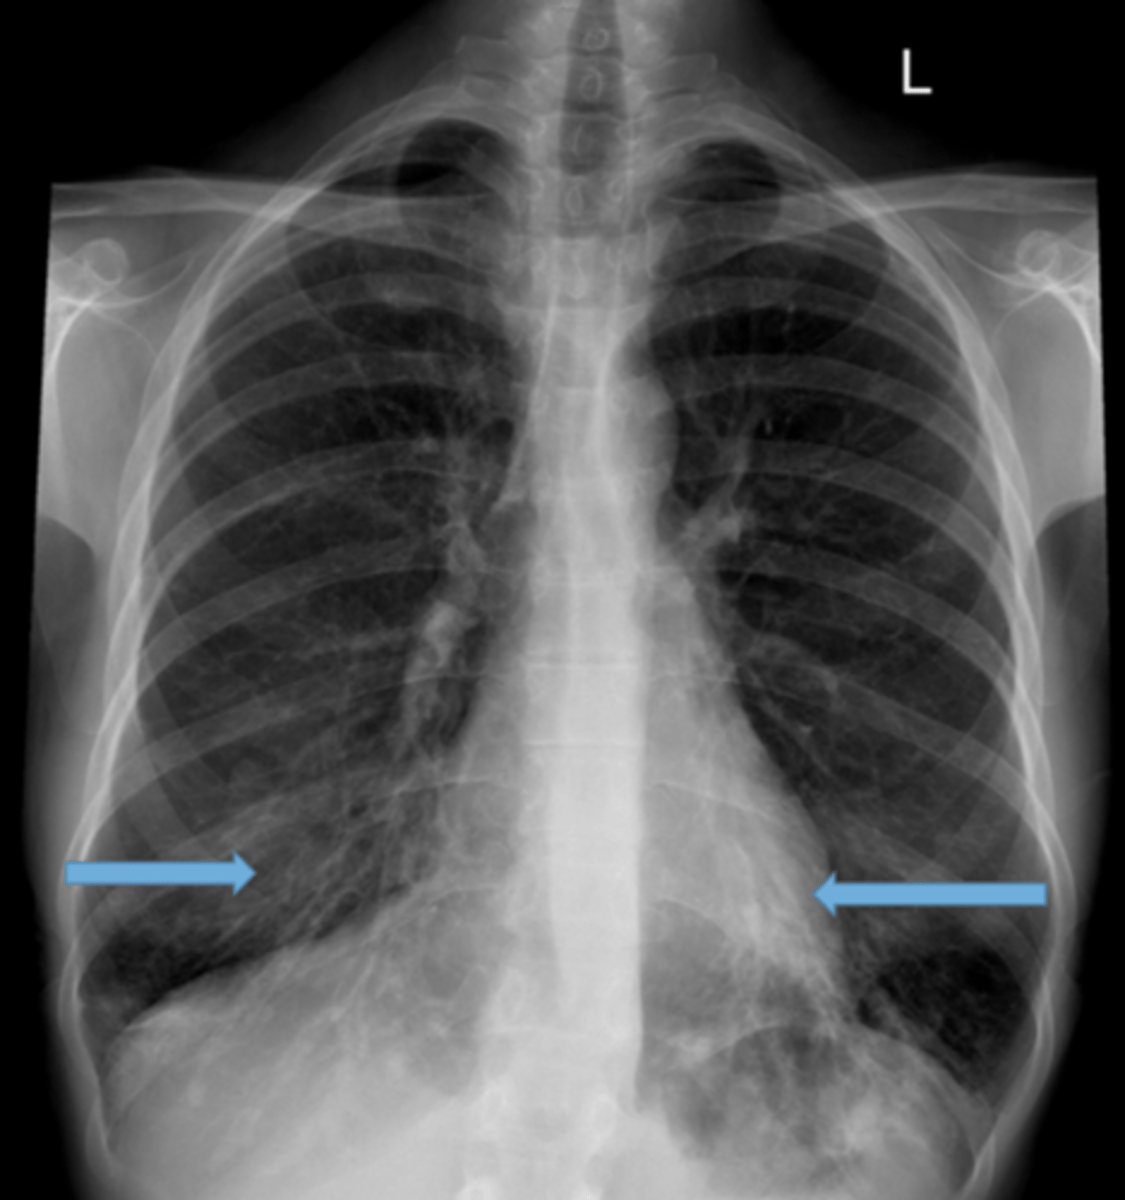

Walls of the bronchi thickened by inflammation or infection, may be diffuse or focal

Bronchiectasis

CXR in affected individuals is often normal or shows non-specific findings

Tram track lines

knowt flashcard image